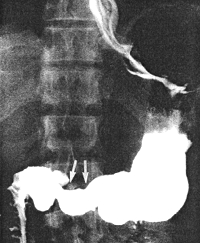

Case 28.1. G.G., 52 year old male. Radiographic examination showed a moderate degree of constant contraction of the pyloric sphincteric cylinder, with absence of normal, cyclical contraction and relaxation; the contraction fixed the pyloric aperture in the open position (Fig. 28.1). The stomach appeared to be hypertonic; rapid emptying of fluid barium occurred. Endoscopic biopsy of the "antral" region revealed acute on chronic gastritis; no evidence of malignancy was seen. Repeat endoscopic biopsy two months later showed acute on chronic inflammatory reaction in the lamina propria, with eosinophylic infiltration and without evidence of intestinal metaplasia. Stainings for Helicobacter pylori were positive. A third endoscopic biopsy two months after the second, showed chronic gastritis with intestinal metaplasia. Stainings for Helicobacter pylori were negative.

![]() |

| Fig. 28.1. Case G.G. Moderate degree of constant contraction of pyloric sphincteric cylinder (arrows). Cyclical activity absent. Pyloric aperture patent |